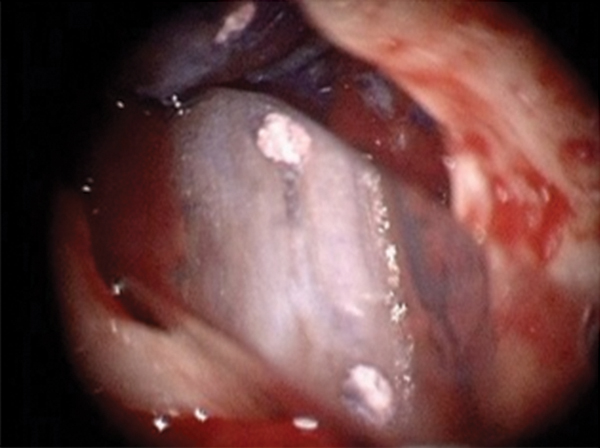

Figure 16. Post apicoectomy. Courtesy of Dr. Sam Kratchman.

Figure 16

Case 3: Apicoectomy and Retrofill

A patient presented with clinical symptoms and radiographic signs of post-endodontic disease (Figure 15). It was determined that the ledge on the mesial canals precluded retreatment and that an apicoectomy was to be performed. After locating the apicoectomy, it was possible to visualize both canals and an obvious isthmus between the two main canals (Figure 16). Retro-preparations were performed in the main canals, and the isthmus between them was grooved and the cavities filled with BC RRM-Putty (Figure 17). At the 20-month follow-up, the patient was asymptomatic and the radiograph showed complete healing (Figure 18).